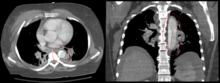

Computed tomography

Computed tomography angiography is a fast, noninvasive test that gives an accurate three-dimensional view of the aorta. These images are produced by taking rapid, thin-cut slices of the chest and abdomen, and combining them in the computer to create cross-sectional slices. To delineate the aorta to the accuracy necessary to make the proper diagnosis, an iodinated contrast material is injected into a peripheral vein. Contrast is injected and the scan performed using a bolus tracking method. This type of scan is timed to an injection to capture the contrast as it enters the aorta. The scan then follows the contrast as it flows though the vessel. It has a sensitivity of 96 to 100% and a specificity of 96 to 100%. Disadvantages include the need for iodinated contrast material and the inability to diagnose the site of the intimal tear.